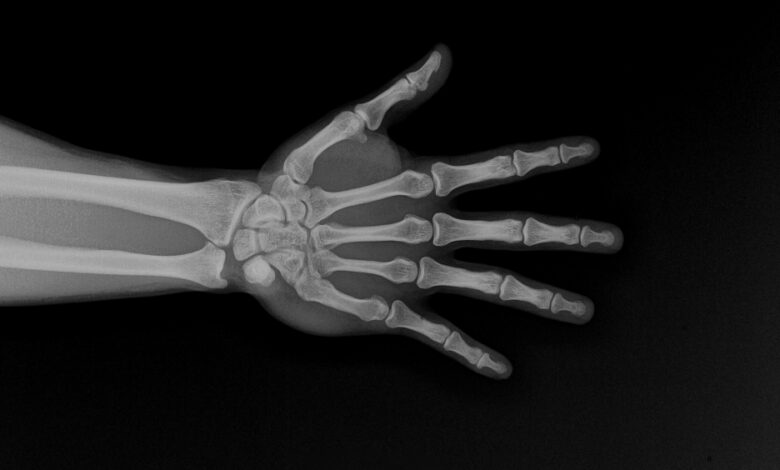

تم العثور على البلاستيك الدقيق ليس فقط في المحيطات وعلى الشواطئ. تم العثور على هذه الجزيئات الصغيرة أيضًا داخل جسم الإنسان ، بما في ذلك الدماغ والحيوانات المنوية والضوء والدم. يدخل البلاستيك الجسم عبر الهواء والماء والطعام. الإطارات والمنسوجات والتعبئة والأشياء التي ألقيت – كل هذا يجلب أصغر الجزيئات في الهواء والتربة والماء. يمكن أن تتحرك الجزيئات الصغيرة مع تدفق الدم وتستقر في الأنسجة.

تصف الدراسة التغيرات في سلوك الخلية والتي تعتبر مهمة لقوة العظام. تم إضعاف الإشارات التي تساهم في نضوج الخلايا ، في حين أن الإشارات التي تسهم في تدمير العظام ، على العكس.

في بعض النماذج ، يميل التوازن لصالح الخلايا العظمية – الخلايا التي تزيل العظم القديم. الإزالة الشديدة للغاية ، التي تسمى ارتشاف العظام ، تجعل الهيكل العظمي أكثر هشاشة مع مرور الوقت.

يفيد الباحثون أيضًا أن البلاستيك الدقيق يمكن أن يخترق العظام الأعمق ، بما في ذلك نخاع العظام. يمكن أن يؤثر اضطراب جهاز نخاع العظم سلبًا على تكوين خلايا الدم وعلى تجديد العظام.

التغييرات في العمر والهرمونية تؤدي بالفعل إلى فقدان كتلة العظام. يمكن أن يؤدي الإجهاد الإضافي من رأب microplasty إلى تفاقم المشكلة ، خاصة في الأشخاص الذين لديهم عوامل خطر أخرى. تتنبأ مؤسسة هشاشة العظام الدولية أن عدد كسور مفصل الورك سوف يتضاعف تقريبًا بحلول عام 2050 مقارنة بعام 2018.